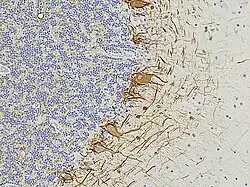

In histological sections of human brain tissue, NF-L can also be visualized using immunostaining. For example, in formalin-fixed and paraffin-embedded sections of the human cerebellum, an antibody specific to NF-L reveals its presence throughout various neuronal compartments[7]. The brown-stained antibody binding highlights the axonal processes of basket cells, the parallel fibers of granule cells,[21][18] the perikarya of Purkinje cells,[21] and other axonal elements. Counterstaining with a blue dye allows for the visualization of cell nuclei, delineating the granular layer on the left side of the section and the molecular layer on the right.[21] These staining patterns underscore the widespread and structurally critical role of NF-L in both developing and mature neurons.[19][18]